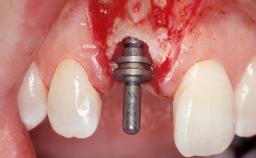

Late Flapless Placement of an Implant in a Maxillary Left Central Incisor Site

A 39-year-old male patient presented with a chief complaint of discomfort and gingival discoloration around his maxillary left central incisor. He was in good general health and was a non-smoker. His past dental history was significant because of the traumatic fracture of tooth 21 in a sporting accident at age 13. Initial dental treatment included endodontic therapy and a full-coverage restoration. The patient became symptomatic 5 years later, when structural failure of the tooth resulted in the dislodgment of the crown. Endodontic retreatment, apical surgery, and post-and-core restoration were performed.

Type of Implants One-Piece

Bone Augmentation Horizontal|Staged

Augmentation Materials Xenogenous|Membrane

Soft Tissue Grafting Simultaneous

Bone Volume Deficient horizontally, requiring prior grafting